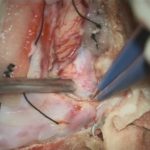

No.’25_41 摘出 前

No.’25_41  摘出 中

No.’25_41 摘出 後